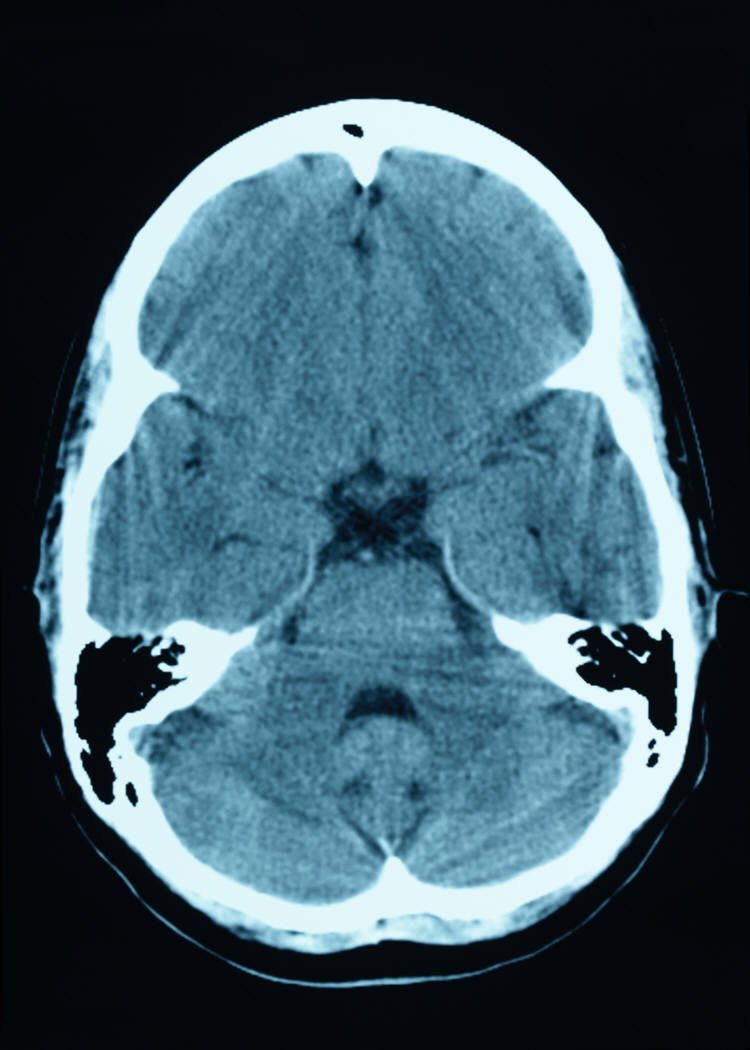

Por eso cada vez se ha ido pensando más en las causas físicas de la transexualidad. Hace años, la revista especializada The Internacional Journal of Transgenderism publicó los resultados de un estudio realizado por varios expertos de la Universidad de Ámsterdam que evidenciaban que realmente existen similitudes estructurales y neuroquímicas entre el cerebro de las personas transexuales y el cerebro típico de las personas del sexo con el que los transexuales se sienten identificados.